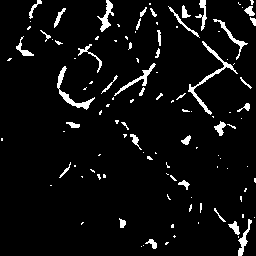

Semantic segmentation of blood vessels is an important task in medical image analysis, but its progress is often hindered by the scarcity of large annotated datasets and the poor generalization of models across different imaging modalities. A key aspect is the tendency of Convolutional Neural Networks (CNNs) to learn texture-based features, which limits their performance when applied to new domains with different visual characteristics. We hypothesize that leveraging geometric priors of vessel shapes, such as their tubular and branching nature, can lead to more robust and data-efficient models. To investigate this, we introduce VessShape, a methodology for generating large-scale 2D synthetic datasets designed to instill a shape bias in segmentation models. VessShape images contain procedurally generated tubular geometries combined with a wide variety of foreground and background textures, encouraging models to learn shape cues rather than textures. We demonstrate that a model pre-trained on VessShape images achieves strong few-shot segmentation performance on two real-world datasets from different domains, requiring only four to ten samples for fine-tuning. Furthermore, the model exhibits notable zero-shot capabilities, effectively segmenting vessels in unseen domains without any target-specific training. Our results indicate that pre-training with a strong shape bias can be an effective strategy to overcome data scarcity and improve model generalization in blood vessel segmentation.